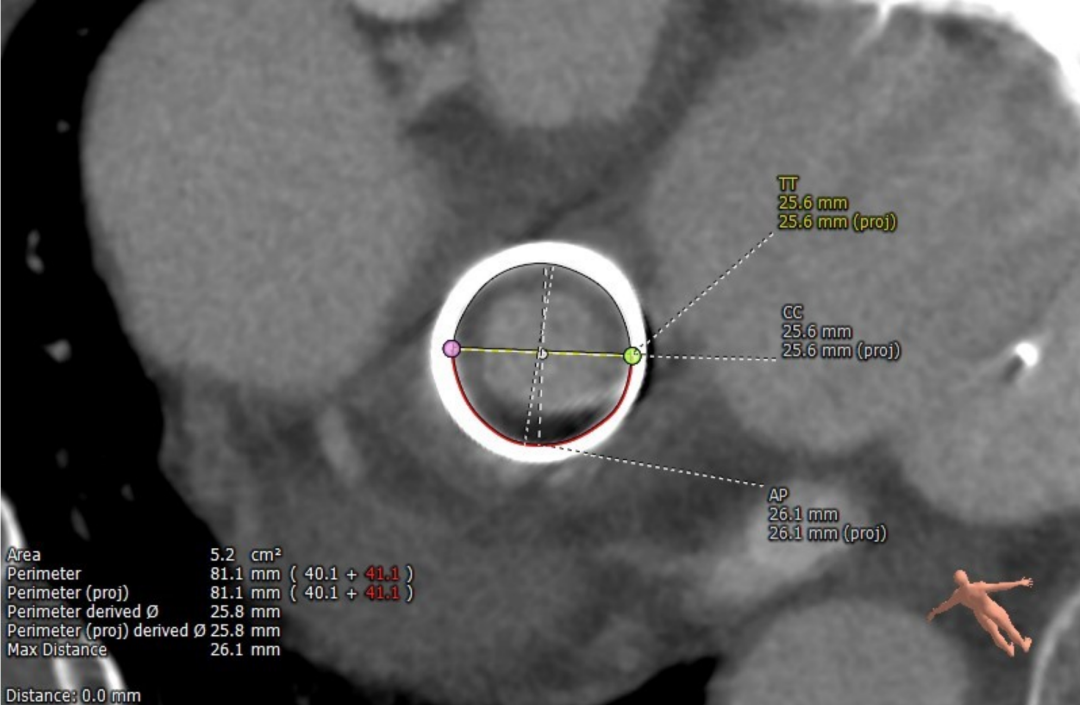

毁损生物瓣瓣架结构 瓣环内径测量

术前经详尽评估患者病情,通过CT重建测量瓣环直径、左室流出道面积。结合之前外科换瓣手术入路,决定采用经心尖途径行二尖瓣“瓣中瓣”手术。术中选用25# Renato®球扩式瓣中瓣,顺利通过心尖途径植入。手术过程顺利,几乎无出血。最终瓣中瓣植入位置理想,功能表现出色,左室造影及经食道超声观察无明显瓣中及瓣周反流。二尖瓣峰值流速由术前2.5m/s降至1.5m/s,平均跨瓣压差由11mmHg降至2.6mmHg。

患者女性,73岁,5年前因“风湿性二尖瓣狭窄,三尖瓣反流,心功能III级,心房颤动”于胸科医院行二尖瓣生物瓣置换+房颤射频消融术,植入27# Epic瓣膜一枚。近日,患者因活动后胸闷、心悸,体力活动能力下降入院。心超提示二尖瓣中重度反流,考虑生物瓣损毁。患者STS评分14.958%,属于常规外科再次换瓣手术高风险患者。